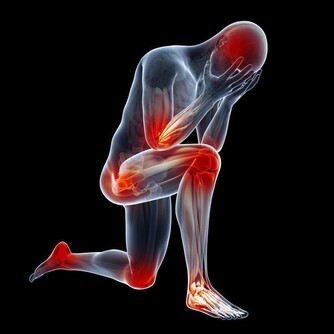

Q:缺乏鈣質會使身體肌肉緊繃?

人體缺乏鈣質時,其實害怕的是血液含鈣量不足,以致於影響身體機能,醫學上稱為低血鈣症,它從神經的傳導訊息到內分泌,甚至是肌肉收縮都有關係。通常低血鈣症會影響三種肌肉:

骨骼肌:缺鈣會讓人肌肉緊繃,無法放鬆。

平滑肌:缺鈣時心臟會亂跳,反而會心律不整,有時可會導致猝死問題。

心肌:與腸胃道的蠕動跟吸收及血管有關,會影響血管收縮。